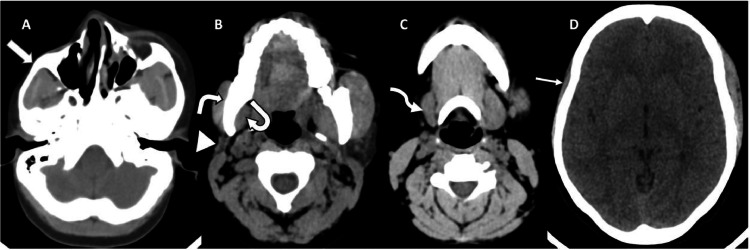

Fig. 2.

(A-D) Axial head CT scan (soft tissue window) showing thinning of the subcutaneous fat and skin over the right malar region (block arrow) (A) as well as atrophy of the right parotid gland (arrowhead) (B), right submandibular gland (squiggle arrow) (C), right masseter muscle (white bent arrow) (B), right medial pterygoid muscle (curved arrow) (B) and right temporalis muscle (straight arrow) (D).